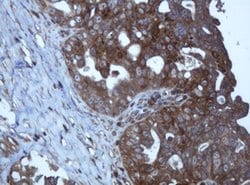

| Immunohistochemistry (Paraffin), Western Blot | |